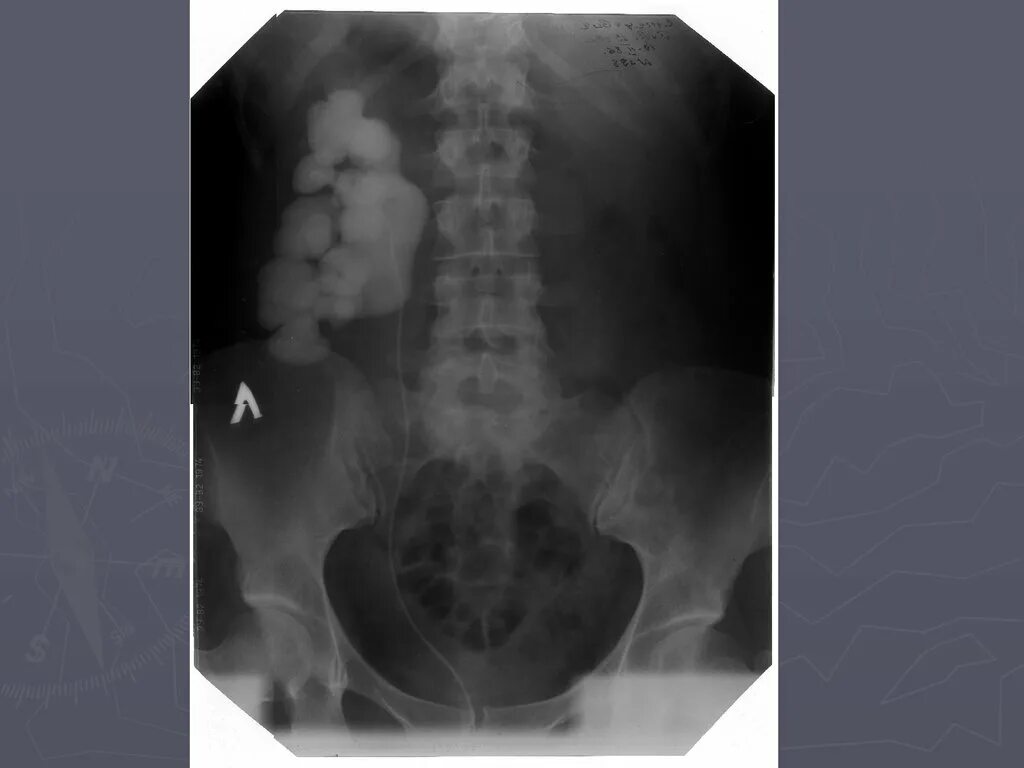

Гидронефроз симптомы у взрослых